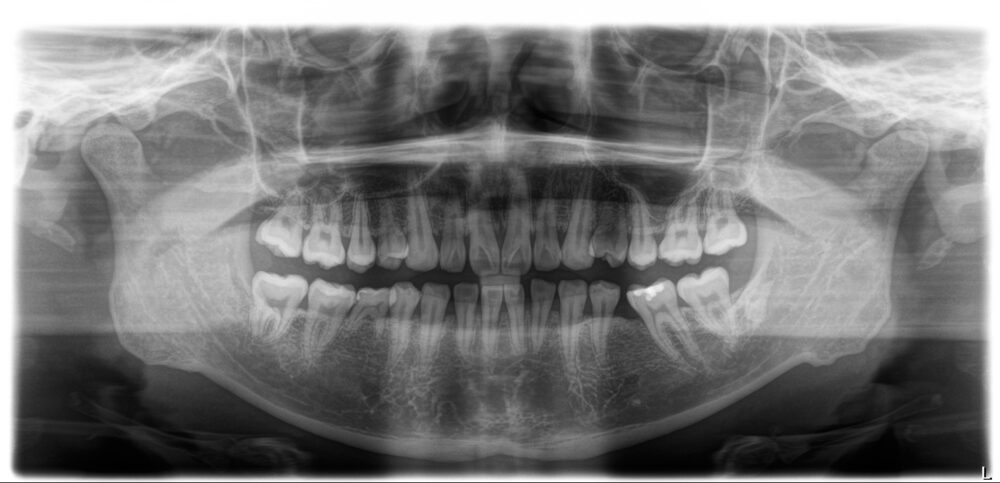

両側とも下の5番目の永久歯が生まれつきありません(先天的欠如歯)。

先天的に永久歯がないことや乳歯が残っていることで他の歯の位置がずれ、上下の顎の関係が狂ってしまいます。その結果、呼吸環境が悪化していことが「歯ぎしり」の一因になっている可能性があることを伝え、咬合診断の上、矯正治療とインプラント治療が必要であることをお話ししました。